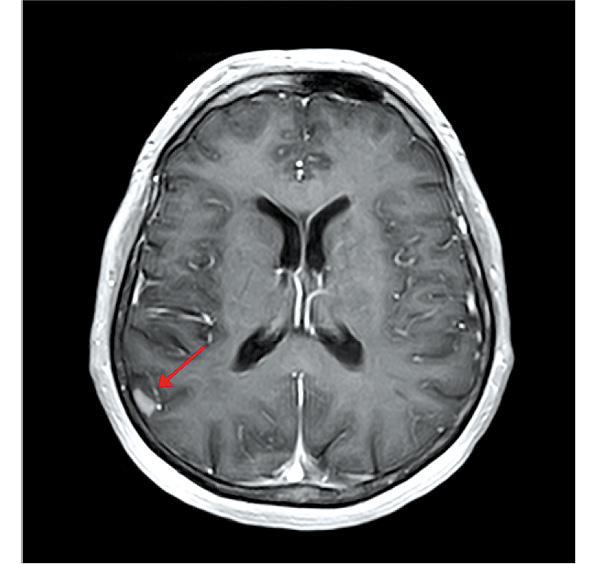

Пациентка продолжала исследуемую терапию, когда в марте 2018 г. на МРТ головного мозга с в/в контрастированием по поводу периодически беспокоящих головных болей выявлен единичный мтс в области головки хвостатого ядра левого полушария большого мозга до 5 мм без перифокального отека (рис. 7). По всей видимости, этот очаг обнаружен случайно, поскольку такой небольшой мтс не должен вызывать симптомы, что обусловливает необходимость регулярного обследования головного мозга у пациентов с распространенной меланомой при помощи МРТ с в/в контрастированием (в процессе терапии и несмотря на достижение глубокого радиологического ответа).

Рис. 7. МРТ головного мозга с в/в контрастированием от 03.2018 г.